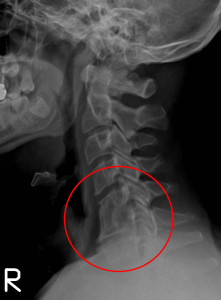

Before I came to Vida Chiropractic I was dealing with severe neck pain and numbness down my arms as well as headaches and restless legs. This wasn’t the first time I had problems with my neck. In 2005 I lost sensation over most of my body and had an emergency fusion at C5/C6. The surgery took care of my emergency situation but didn’t correct the underlying problem.

I started getting neck pain again that progressively got worse. Soon it was causing numbness in my arms as well. It got so bad that I wasn’t able to work anymore. I was in constant pain and taking Tylenol 3 all the time. This problem went on for years and the only answer the doctors had was to put me on the waiting list for another surgery to fuse the areas above and below my first fusion. I was frustrated and depressed because of how bad the pain was but also because I couldn’t be there for my family. I couldn’t work, couldn’t look after the house, couldn’t do many things with my kids.

I met the doctors from Vida Chiropractic at a home show in February 2014. In the office they did an exam of my spine and looked at my x-rays and MRIs and told me they could help. I was a little unsure at first but I knew I had to do something and didn’t really want another surgery. I started getting adjusted and very quickly noticed improvements. The range of motion in my neck improved dramatically, the numbness in my arms started going away and I no longer get headaches.

Even though I’d been to other chiropractors I’d never had postural weight bearing x-rays of my spine taken. Those x-rays showed a big problem in my spine, especially my neck. I decided to start getting adjusted and have been so happy with the improvements. I remember waking up for the first time in the night not from pain but because I had to go to the bathroom. I don’t take prescription meds, I can sleep, go for walks and I feel positive! I’ve also lost 13 lbs because I’m out and about again. I can do left side shoulder checks while driving and don’t need to have an extra pillow behind my back when I’m sitting in the car.